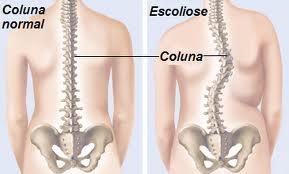

Escoliose nas crianças e adolescentes

Uma criança saudável com a postura errada na sala de aula, frente ao computador ou em suas atividades diárias tem uma grande tendência a desenvolver retrações musculares e fixações articulares por causa do tempo em que permanecem exercendo apenas um tipo de postura. Mais tarde essa postura pode levar a problemas de coluna, tornam-se estudantes […]